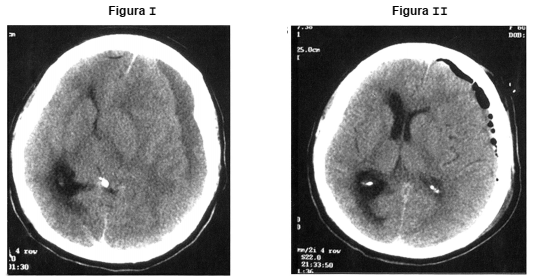

Homem de 66 anos apresentou rebaixamento de nível de consciência e episódio convulsivo. Abaixo, a Figura I mostra a tomografia de crânio na admissão e a Figura II após tratamento.

A conduta terapêutica fundamental provavelmente foi